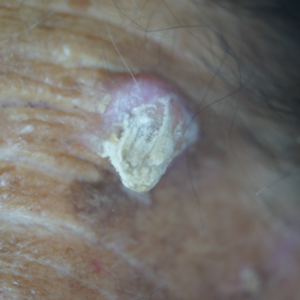

Squamous cell carcinoma looks like warts that crust and sometimes bleed. This cancer can also appear as red patches on the skin, open sores that don’t heal for weeks, or an elevated growth that grows rapidly.